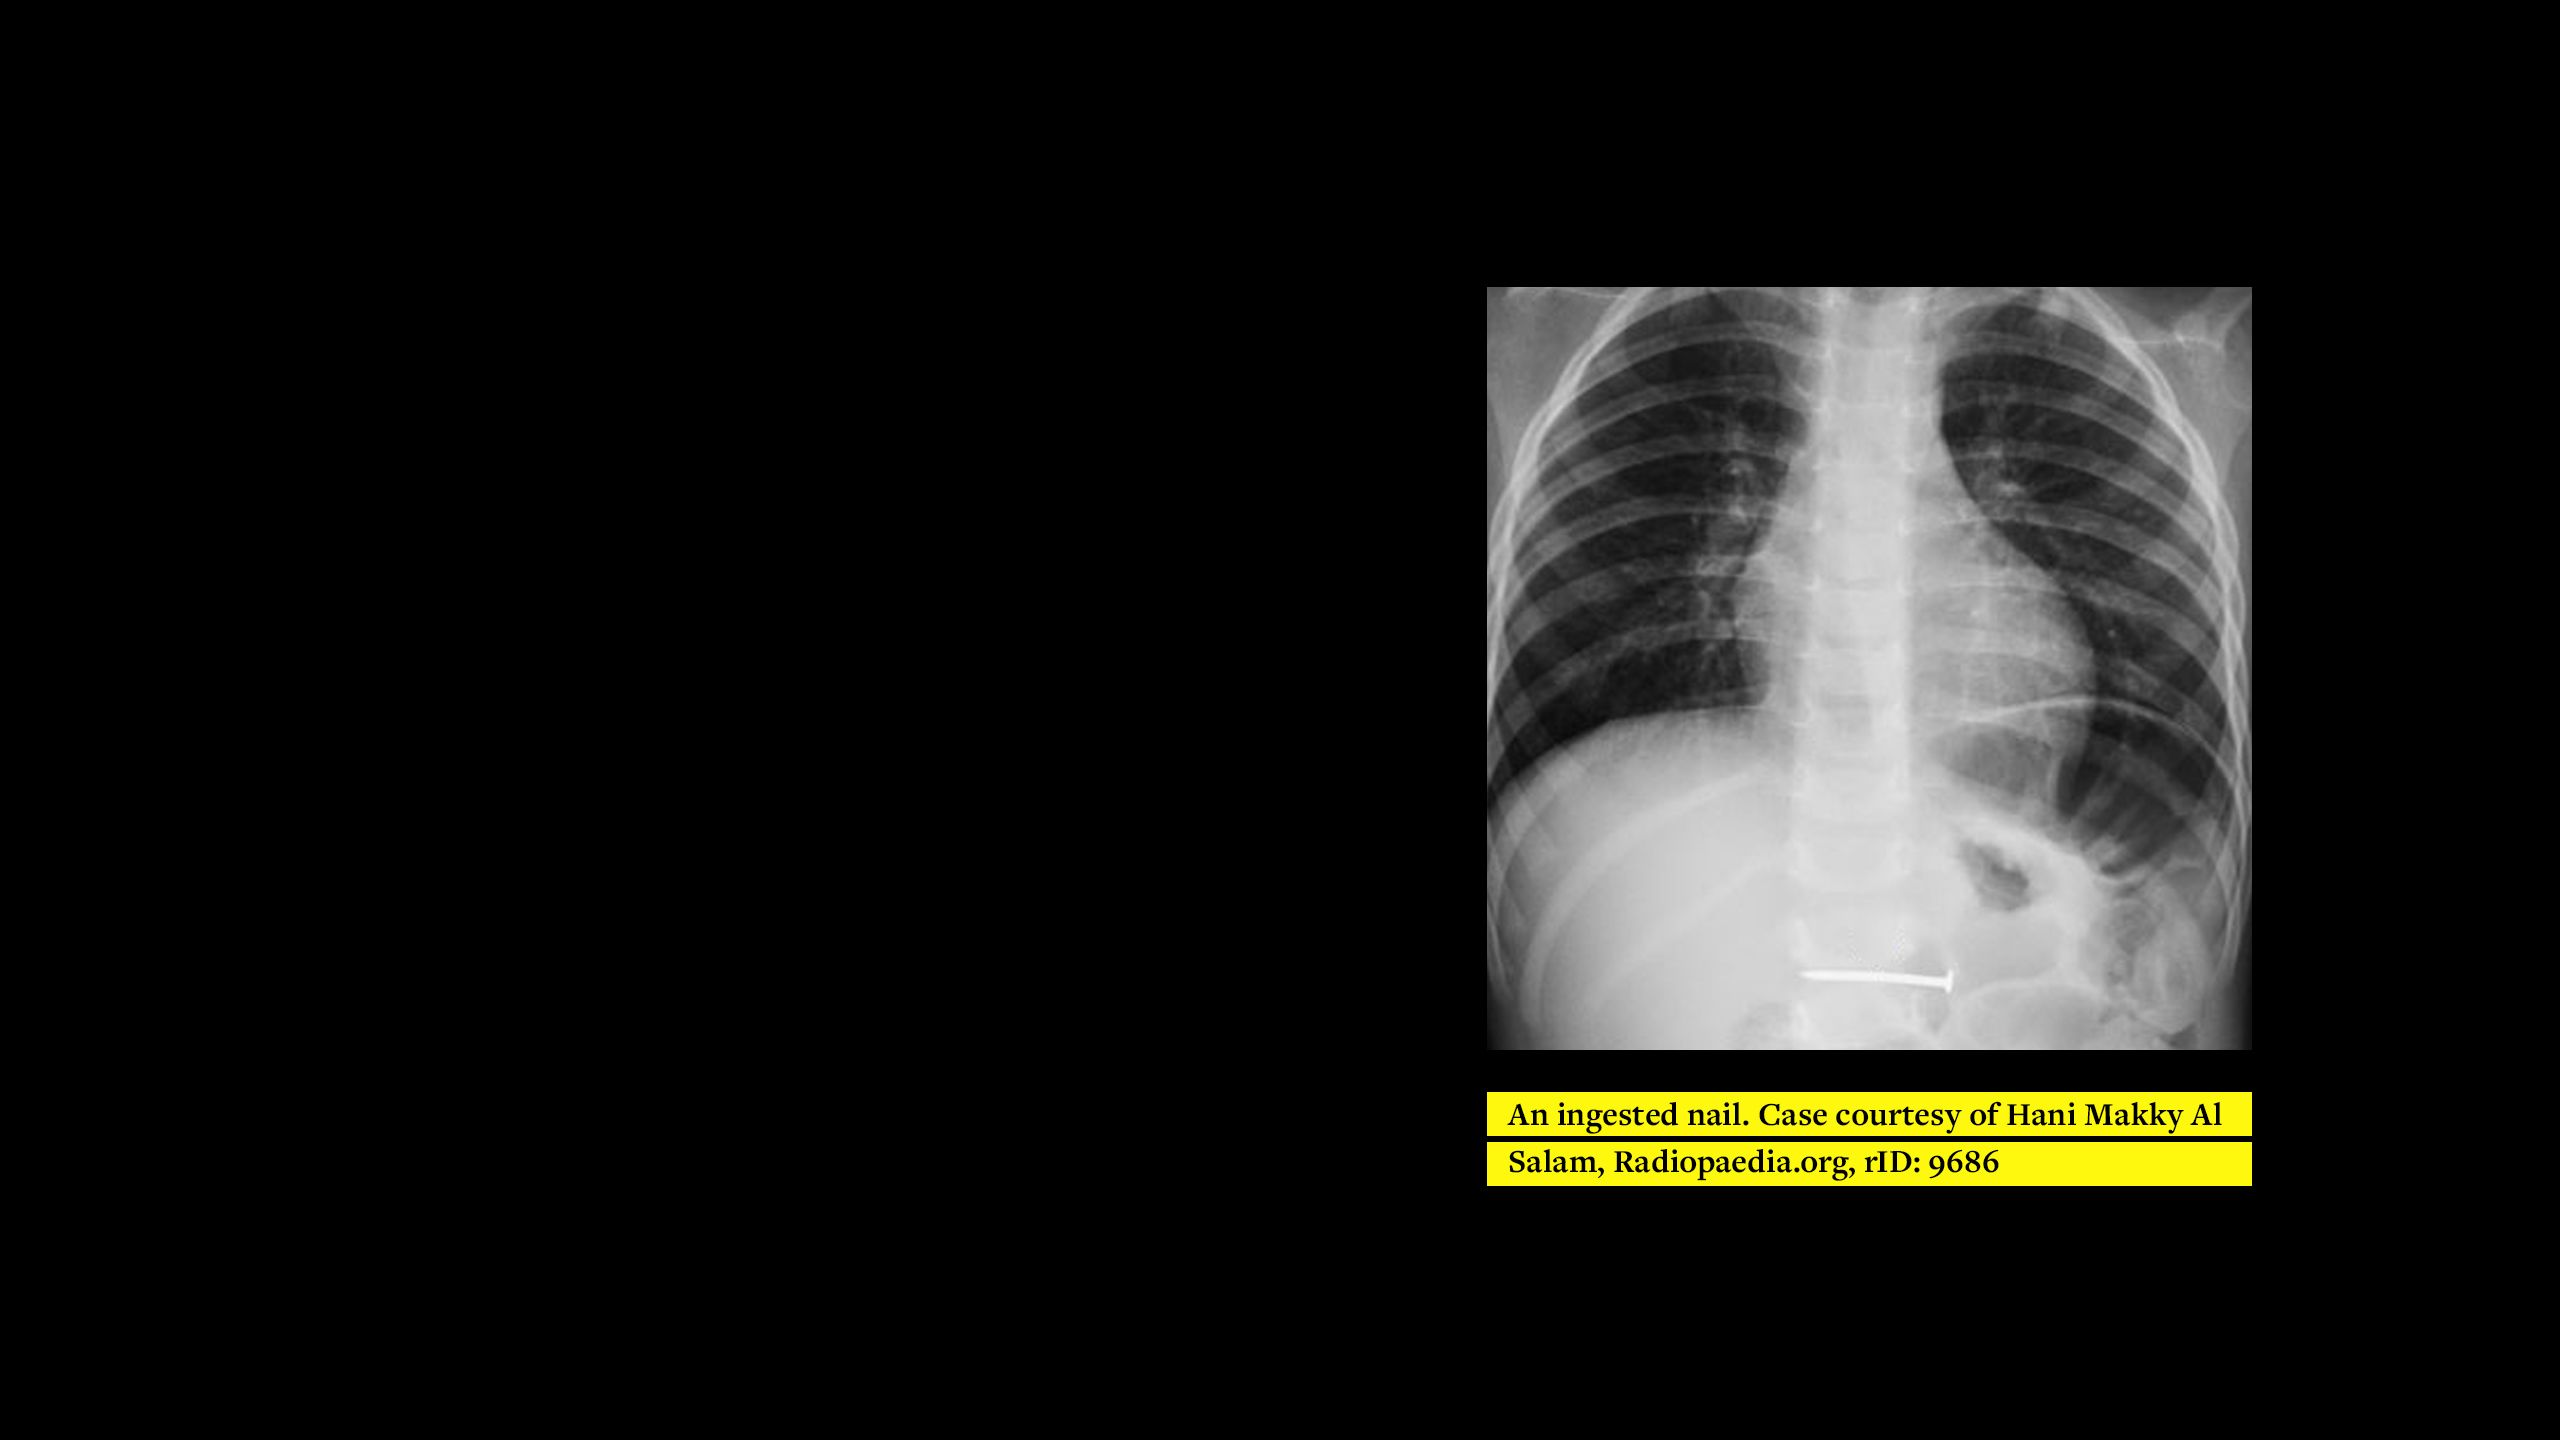

Plain film radiographs have been suggested for unconscious/unresponsive patients1 but the routine use of imaging for MRI screening is limited to localising metallic intra-ocular foreign bodies. However, if medical images are available, should they be routinely used for MRI screening for all patients to ensure the completeness of an MRI screening questionnaire?

The training describes the appearance and most common locations of each implant and tries to explain various ways of differentiating between implants where possible. The reason for implantation is also stated to further assist identification and allow correlations to be made with the patient’s given information and medical records.